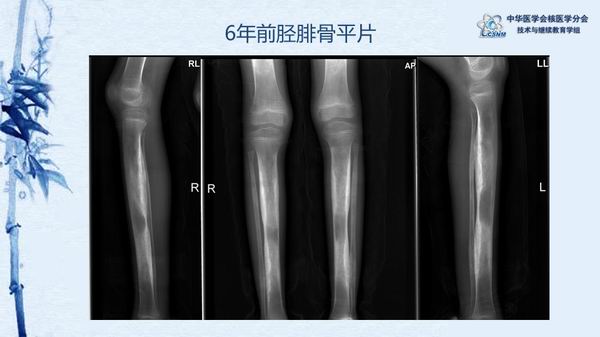

病例85:進(jìn)行性骨干發(fā)育不全一例-張瑩瑩 李鳳岐